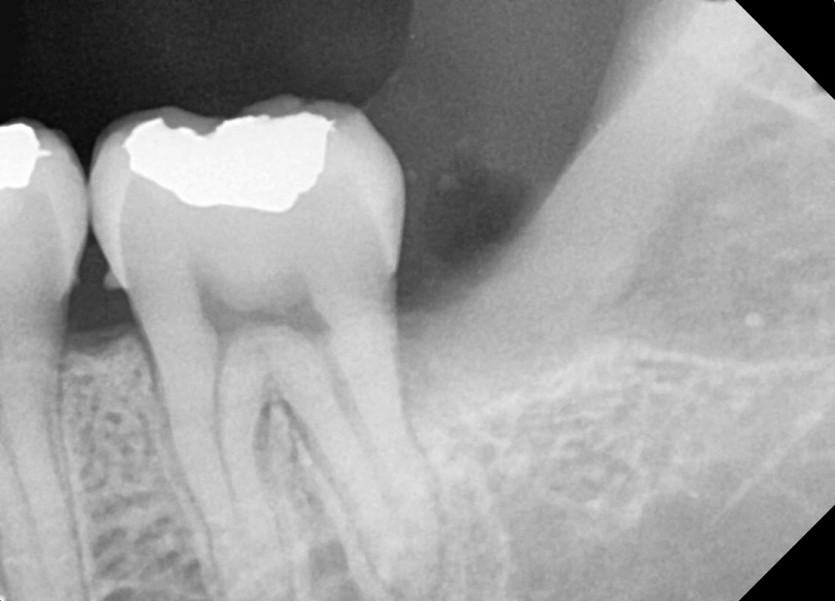

#38, 48 사랑니 발치

구강외과 전문의가 당일발치했습니다.